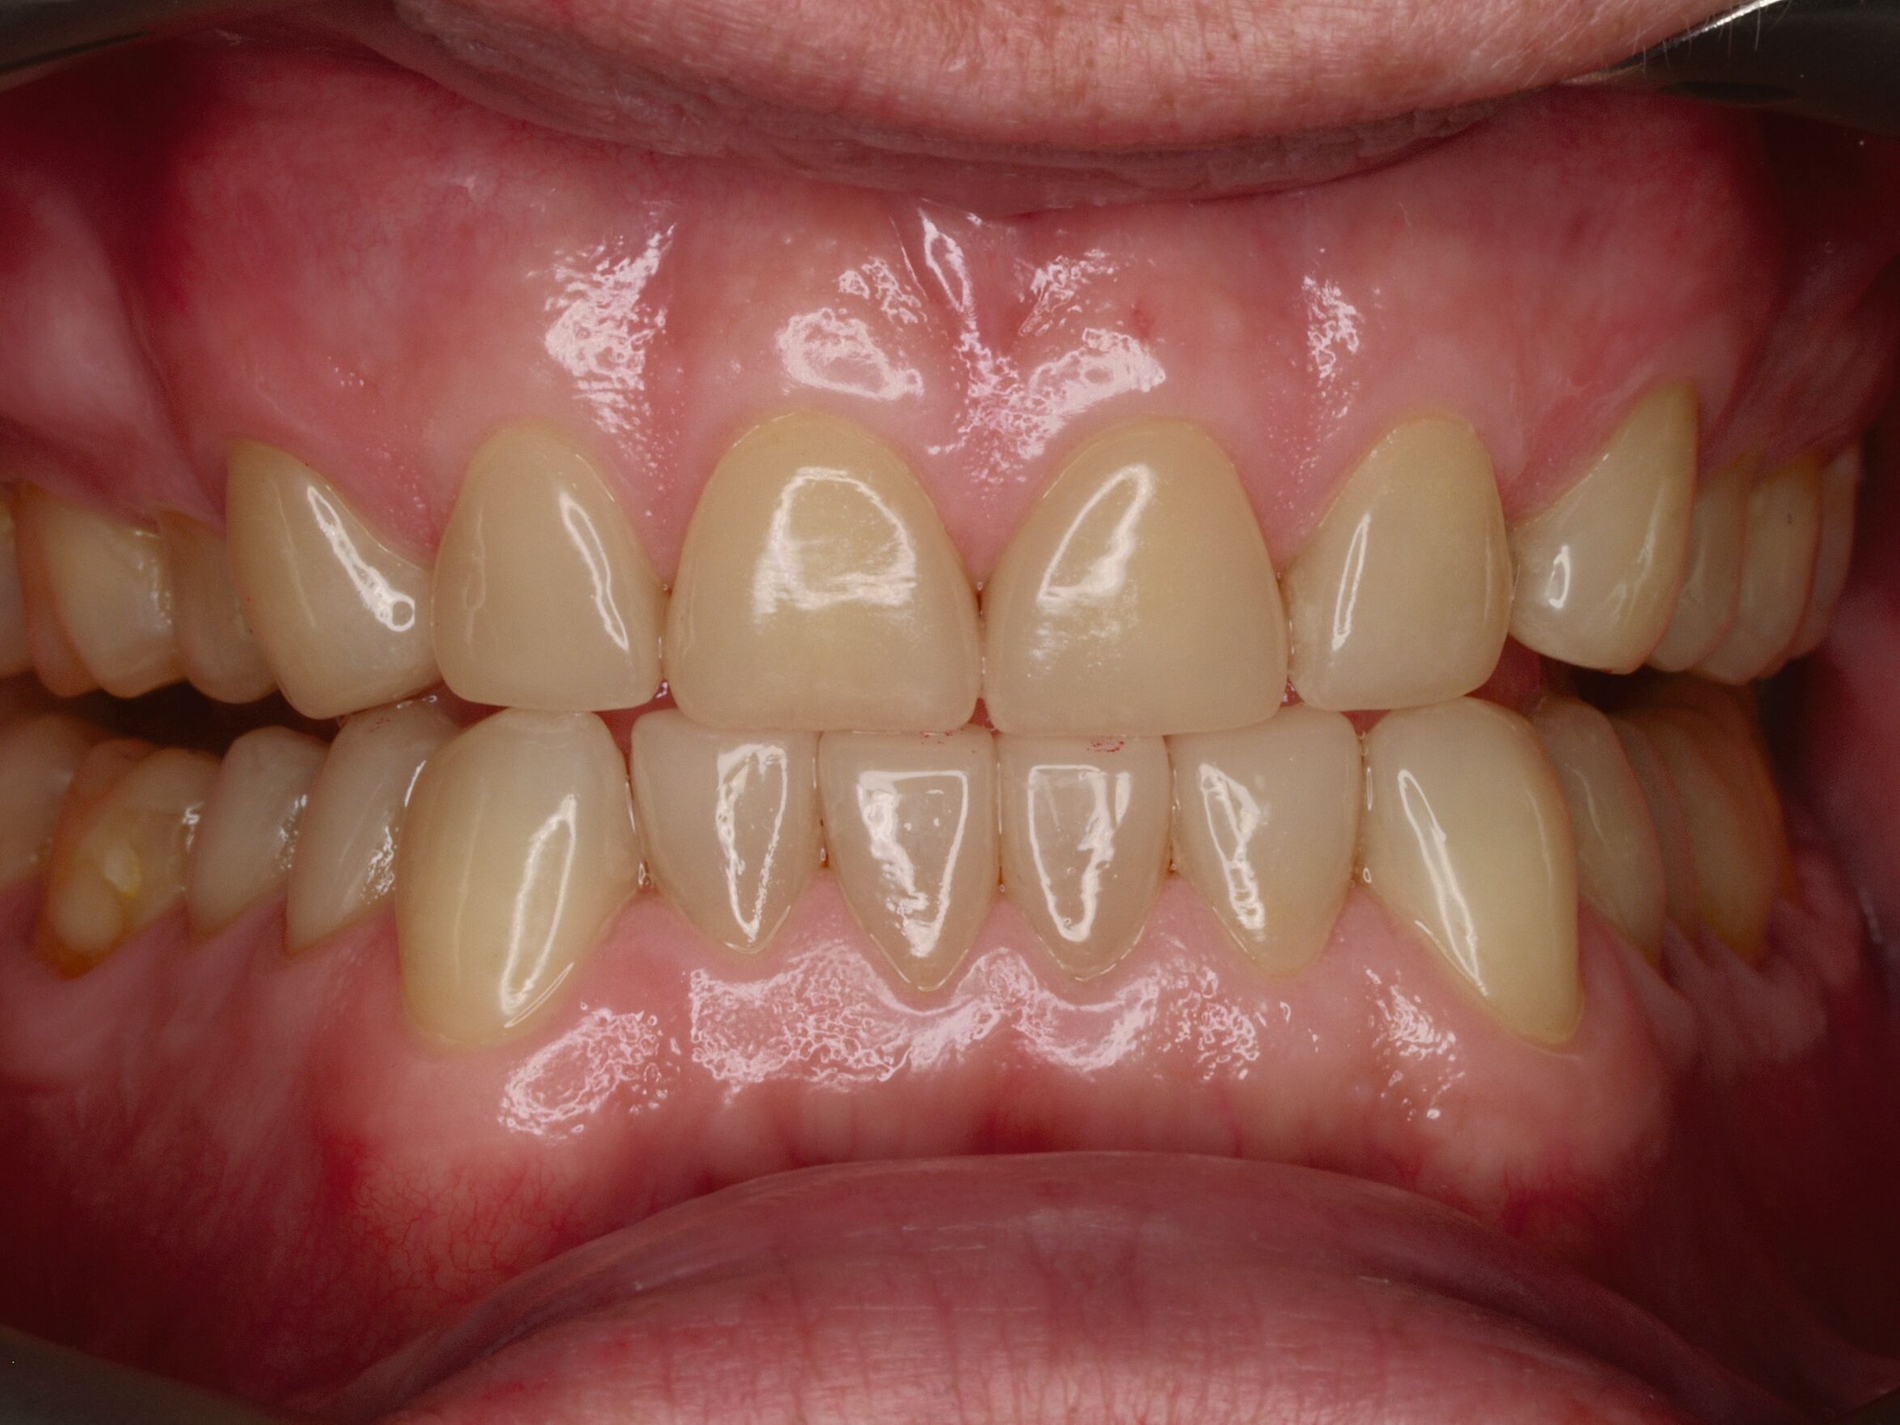

Das unter Beteiligung des Autors entwickelte Tooth Wear Evaluation System (TWES) 2.0 [Wetselaar et al., 2020] identifiziert per Screening Patienten mit erhöhten Verschleißwerten, vergleichbar mit dem PSI in der Parodontologie oder dem CMD-Kurzbefund. Bei auffälligen Werten folgt ein differenzierter Zahnverschleiß-Status einschließlich der Erfassung oraler und vestibulärer Substanzverluste [Wetselaar et al., 2016 sowie von Pathologie-Symptomen und einer strukturierten Diagnose [Tonetti und Sanz, 2019; Wetselaar, 2020]. Den Einsatz in der Praxis illustriert der in den Abbildungen beschriebene Patientenfall aus dem CMD-Centrum Hamburg-Eppendorf.

Im Beispiel ist daher die Diagnose ein generalisierter erheblicher und lokalisierter moderater pathologischer Zahnverschleiß überwiegend mechanischer und zudem chemischer Ursache. Die sich daraus ableitende Erkenntnis ist, dass in allen Sextanten Zähne freiliegende Dentinkerne aufweisen (generalisierter moderater Zahnverschleiß), dass darüber hinaus Zähne erheblich geschädigt und somit gefährdet sind, dass Merkmale eines pathologischen Geschehens bestehen – und dass als Ursache neben dem dominierenden Bruxismus ein Säureeinfluss hinzukommt.

Auch wenn Restaurationen nach Möglichkeit vermieden werden sollten, ist deren Verfügbarkeit für die Betroffenen individuell höchst wichtig, weil sie bestehende Schmerzen beseitigt, die verlorengegangene Kauleistung wiederherstellt und ästhetische und nicht zuletzt auch phonetische Einschränkungen aufhebt. Bei dem in den Abbildungen beschriebenen Fall korrelierte der erhebliche Zahnverschleiß mit der Lokalisation der Zahnschmerzen des Patienten. Direkte Restaurationen mit Kompositen hatten keinen Bestand. Die durchgeführte restaurative Behandlung hingegen hat Bestand, die Schmerzen waren danach umgehend verschwunden und sind seit zehn Jahren nicht wiedergekehrt.

Dabei führt die Verfügbarkeit hochfester Dentalkeramiken heute zu viel weniger invasiven Restaurationen als früher durchgängig übliche metallkeramische Kronen, und die Transluzenz der keramischen Werkstoffe ermöglicht zudem natürlichere Restaurationen. Der beschriebene Behandlungsfall zeigt, wie eine mehrstufige Zahnverschleiß-Diagnostik im Praxisalltag umgesetzt wird, mit initialem Zahnverschleiß-Screening und einer im Bedarfsfall erfolgenden erweiterten Diagnostik per Zahnverschleiß-Status.